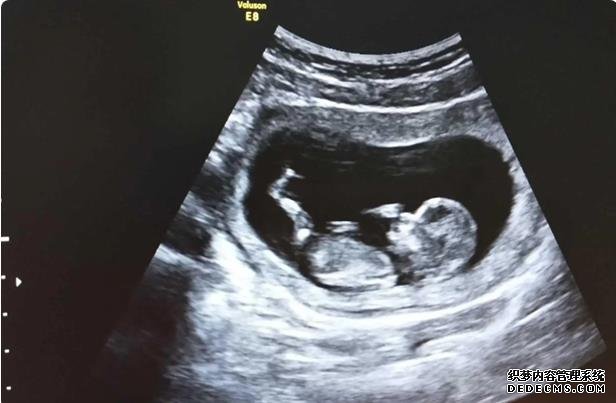

在胚胎移植后的14天,女方需要去醫院進行血液HCG檢測,以確定移植胚胎是否著床,即是否懷孕,如果懷孕,就需要做B超檢查,這部分的費用以醫院收費為準。

實際上孕婦長時間保持一個姿勢,無論是站著還是躺著,胎兒都不會喜歡,孕婦可以根據實際情況來調整自己的姿勢,可以每隔一段時間就調整一下姿勢,這樣是有利于胎兒發育的,注意盡量不要長期保持一個姿勢不動。孕婦在日常生活中要注意休息,同時也要注意運動,長時間的臥床和久站都是不好的,要注意勞逸結合,這樣才能維持良好的胎盤血供。